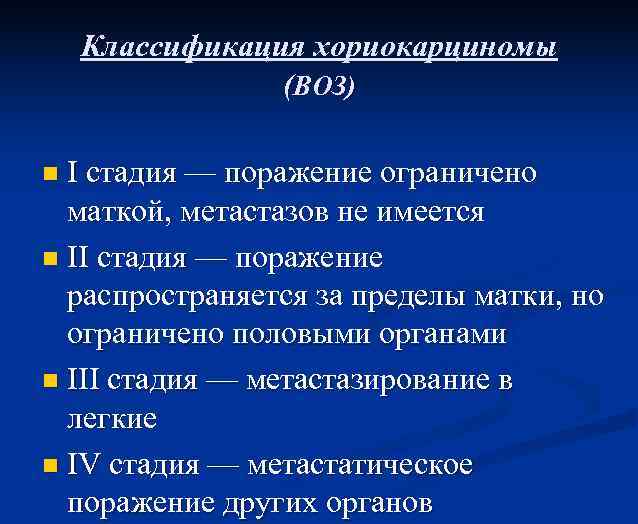

Классификация хориокарциномы (ВОЗ) I стадия — поражение ограничено маткой, метастазов не имеется n II стадия — поражение распространяется за пределы матки, но ограничено половыми органами n III стадия — метастазирование в легкие n IV стадия — метастатическое поражение других органов n